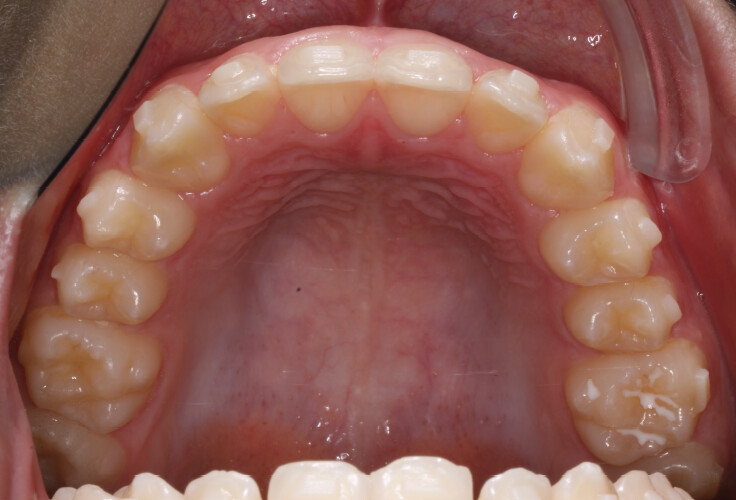

Um paciente do sexo masculino, com 13 anos de idade, apresentou-se com uma mordida profunda, caracterizada pela cobertura quase completa dos incisivos mandibulares. A avaliação clínica revelou apinhamento em ambas as arcadas, rotações dentárias e proclinação dos incisivos laterais superiores, contribuindo para as preocupações estéticas do paciente. O perfil facial era retrusivo, consistente com retrognatismo mandibular, e não foram detectadas anomalias periodontais significativas.

O paciente apresentava uma relação esquelética de Classe II com molares e caninos bilaterais em Classe II e um padrão dentário de Classe II divisão 2. A mordida profunda estava associada a um apinhamento anteroinferior e a uma curva de Spee acentuada. A análise facial revelou boa simetria, um terço facial inferior ligeiramente aumentado e um perfil convexo caracterizado por retrusão mandibular e do mento. A competência labial estava ligeiramente reduzida, com diminuição do ângulo nasolabial e leve tensão do músculo mentoniano, fatores que comprometiam a harmonia facial global.

- Expansão da arcada para resolver o apinhamento e melhorar a coordenação transversal;